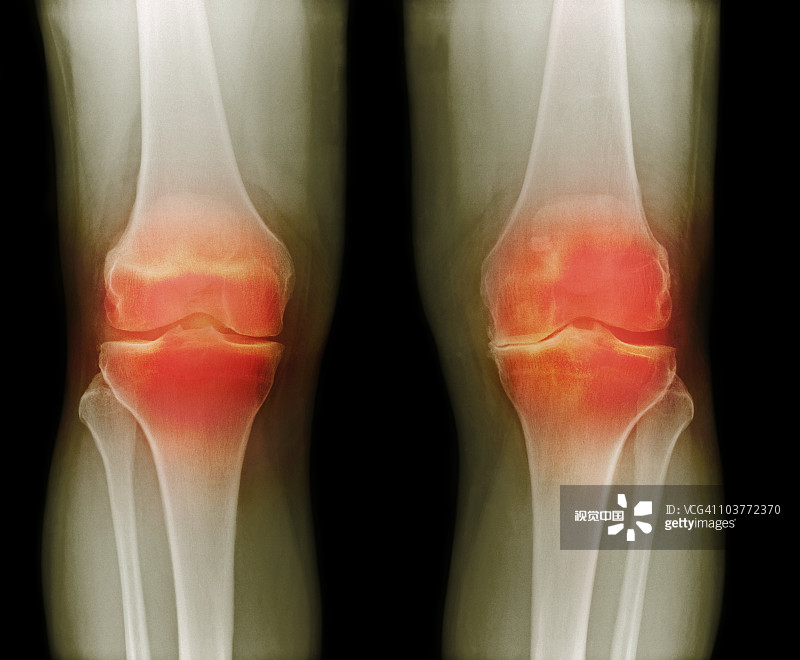

適應癥:膝骨關節(jié)炎

貴醫(yī)附院 | 人臍帶間充質干細胞治療膝骨關節(jié)炎患者的1期臨床試驗